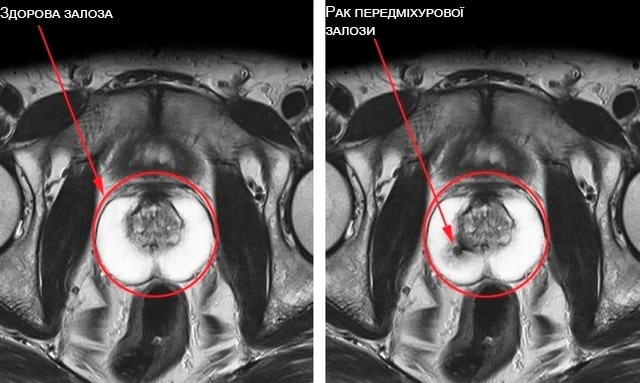

Boli legate de glanda prostatică: prostatită, adenom, cancer de prostată (în decurs de 3-4 ani)

Practic toate problemele cu prostata la bărbați apar din cauza stagnării lichidului seminal. Deoarece Vigrandex readuce sexul în viața bărbatului, se elimină stagnarea. În plus, Vigrandex conține multe componente active, care influențează țesutul glandei. Vigrandex – unul dintre cele mai bune preparate nu doar pentru restabilirea potenței, ci și pentru tratamentul prostatitei, precum și prevenirea cancerului de prostată.

Cancerul de prostată se dezvoltă la toți impotenții în decurs de 8-12 ani. Singura posibilitate de a-l evita este să faceți sex până la bătrânețe (cel puțin până la 80 de ani)